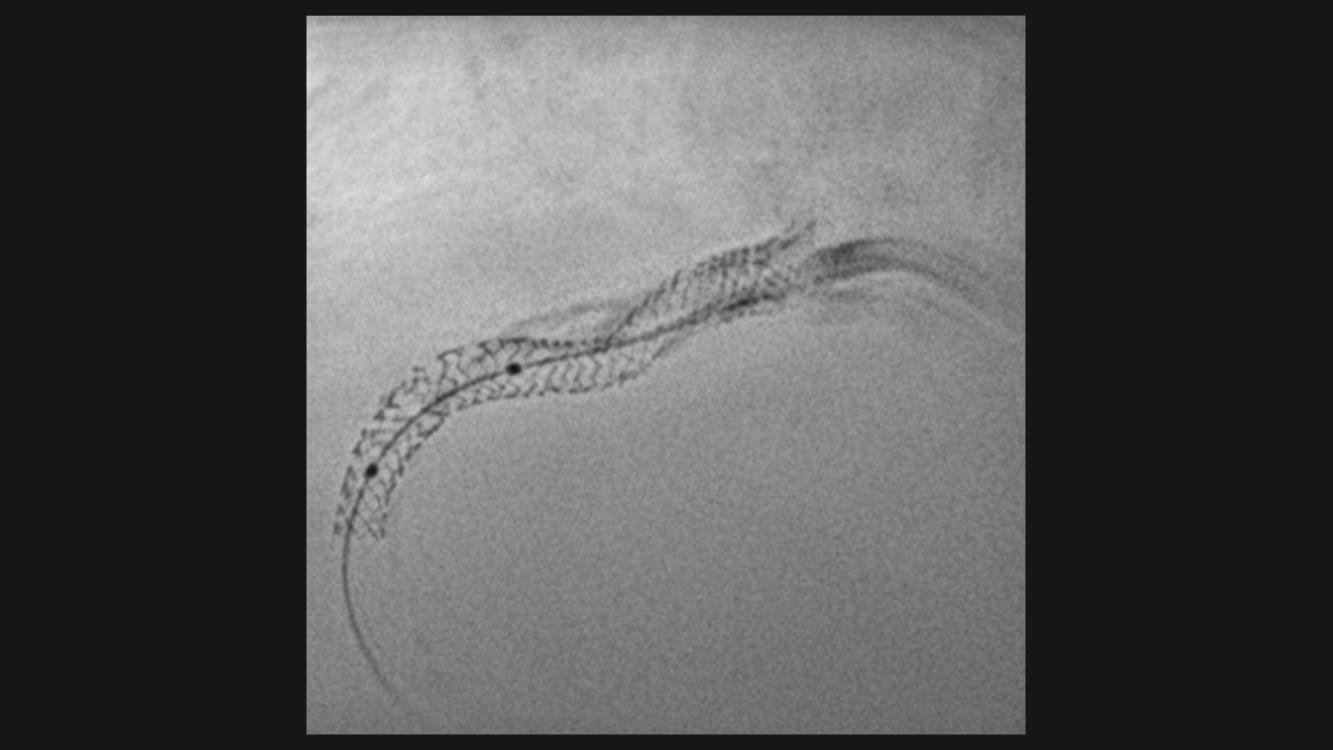

ClearStent Live

Real-time stent enhancement

Courtesy of Universitätsklinikum Erlangen, Germany

ClearStent Live allowing real-time verification of stent positioning while moving the device

- is integrated into the ARTIS systems, without the need of an additional workstation;

- supports complex procedures like kissing stents, skirting technique, and adjacent stents;

- offers the potential to speed up procedures and save contrast agent.